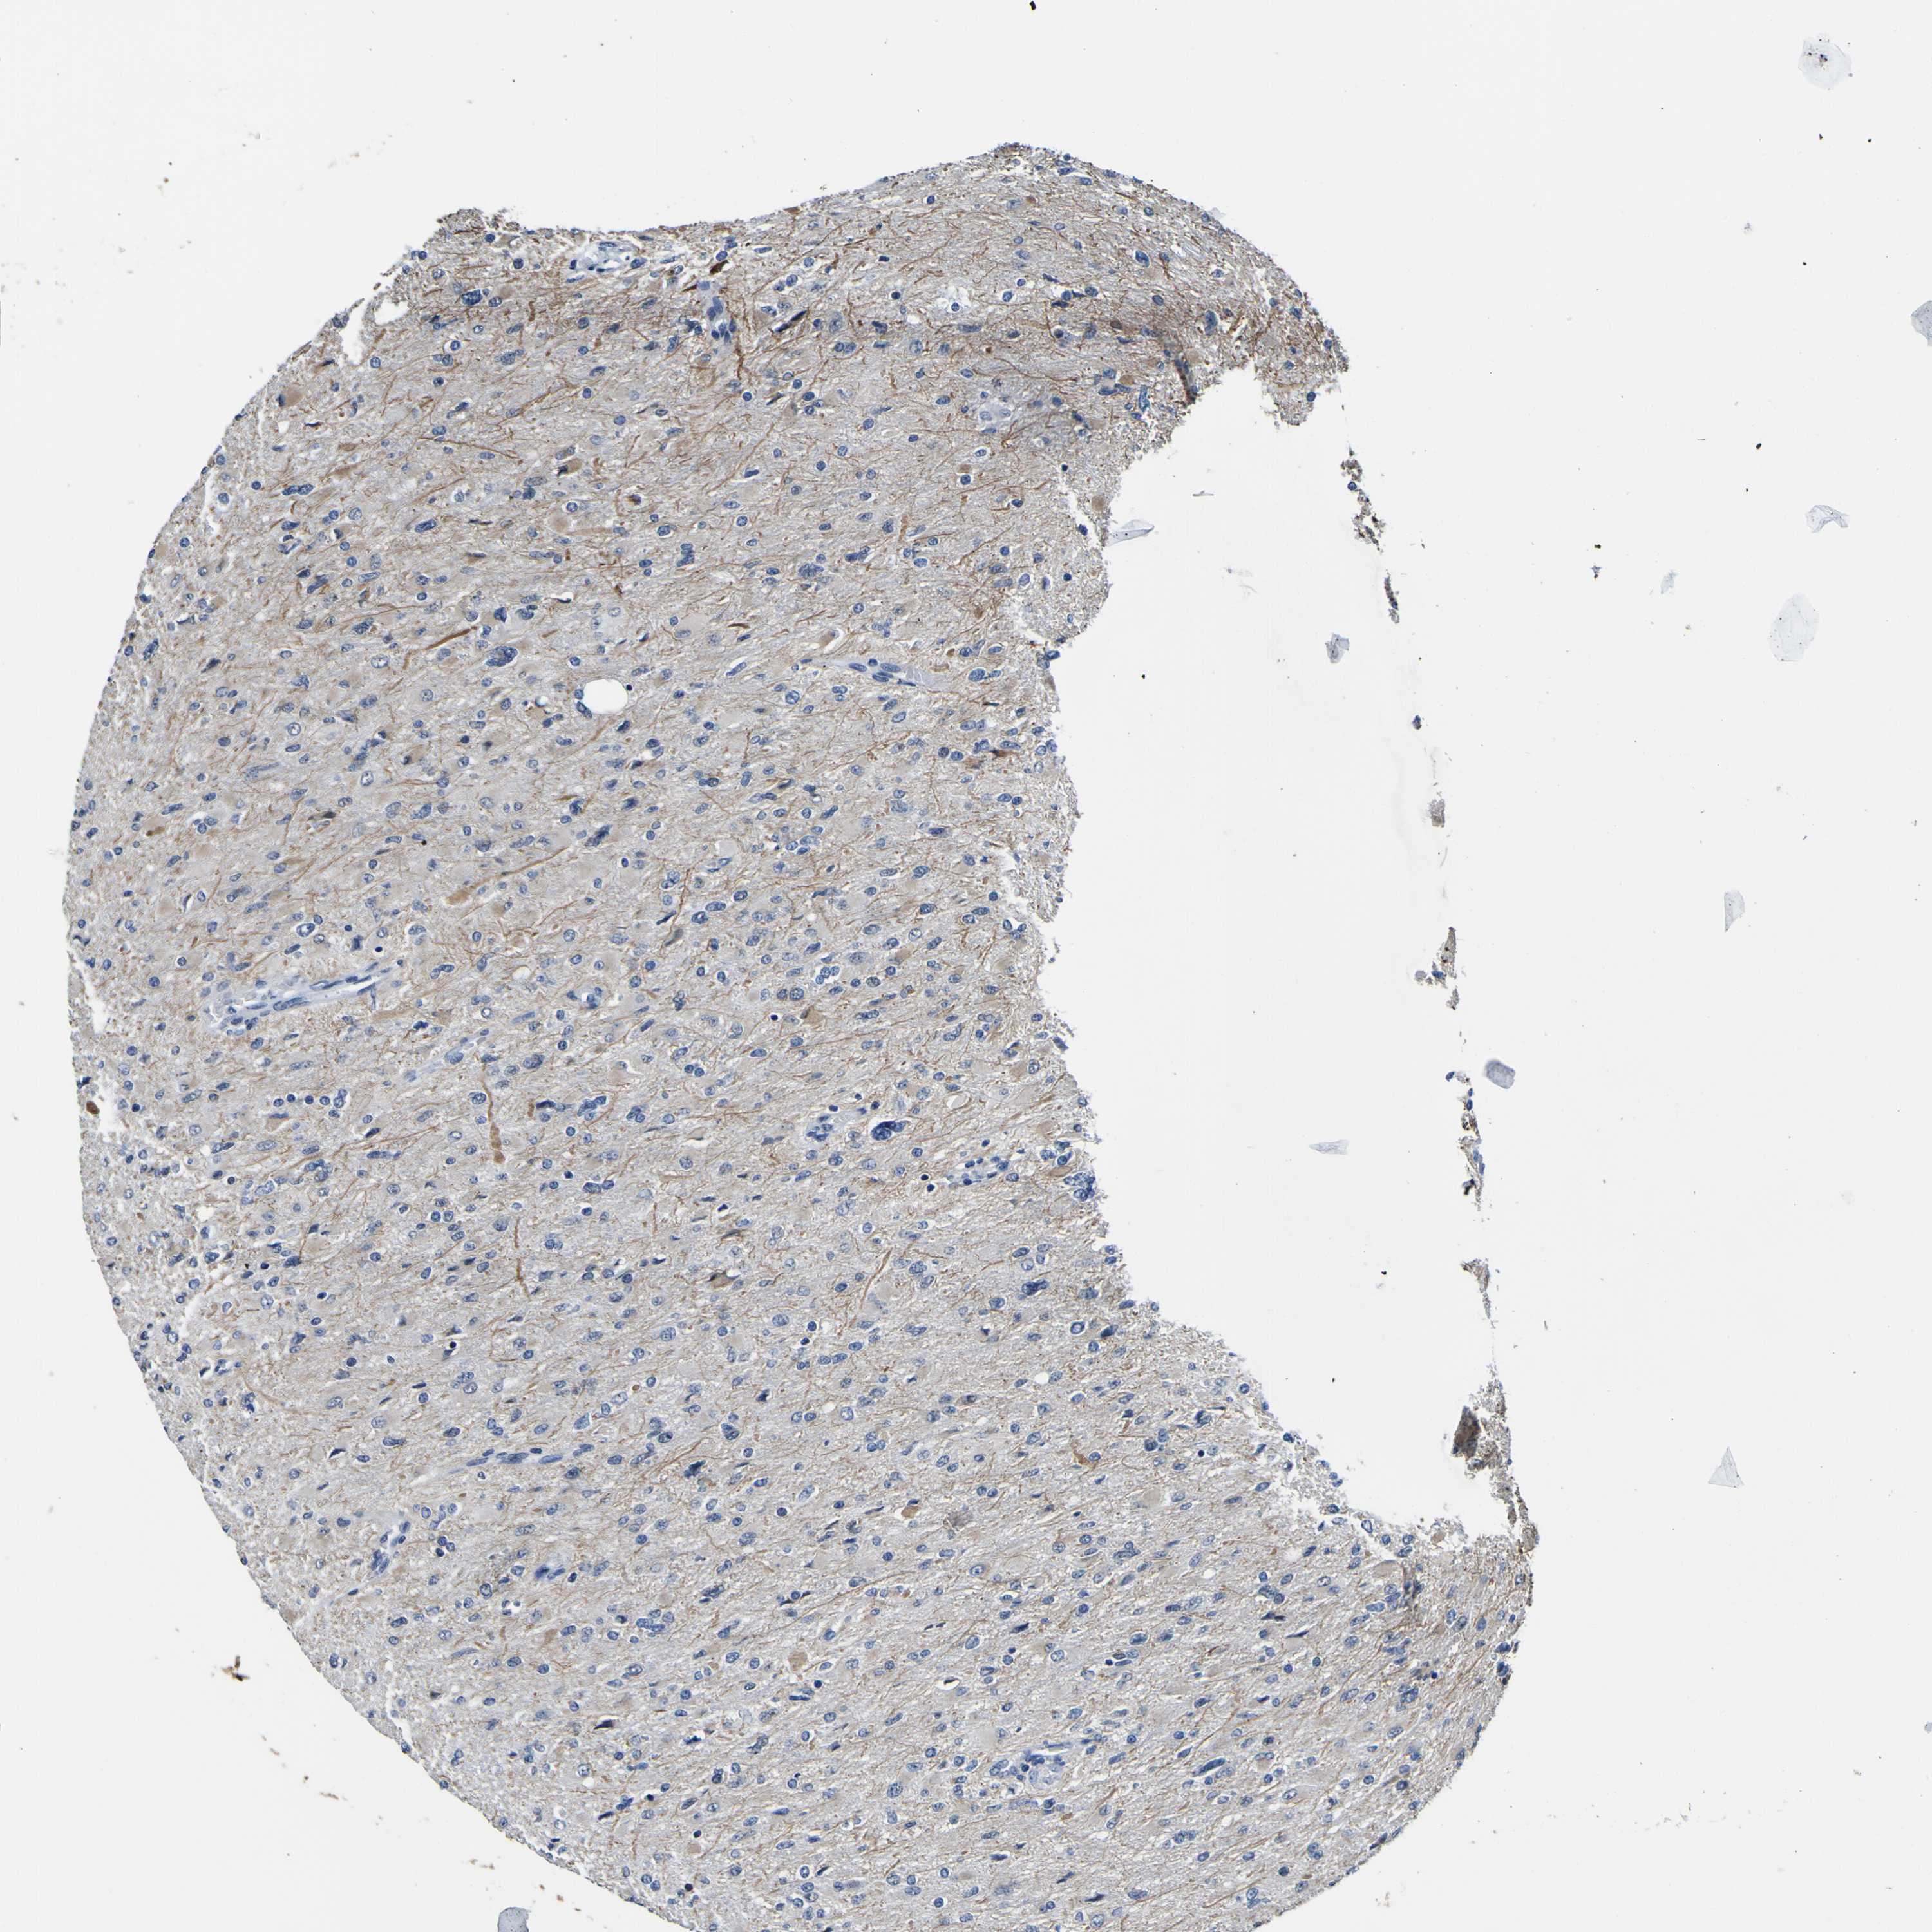

GLIOMA - Protein expressioni

A mouse-over function shows sample information and annotation data. Click on an image to view it in a full screen mode. Samples can be filtered based on level of antibody staining by selecting one or several of the following categories: high, medium, low and not detected. The assay and annotation is described here.

Note that samples used for immunohistochemistry by the Human Protein Atlas do not correspond to samples in the TCGA dataset.

Antibody stainingi

Antibody staining in the annotated cell types in the current human tissue is reported as not detected, low, medium, or high, based on conventional immunohistochemistry profiling in selected tissues. This score is based on the combination of the staining intensity and fraction of stained cells.

Each image is clickable and will lead to virtual microscopy that enables deeper exploration of all samples and also displays staining intensity scores, fraction scores and subcellular localization as well as patient and tissue information for each sample.

Antibody HPA012306

Staining

High

Medium

Low

Not detected

Intensity

Strong

Moderate

Weak

Negative

Quantity

>75%

75%-25%

<25%

None

Location

Nuclear

Cytoplasmic/membranous

Cytoplasmic/membranous,nuclear

Glioma, malignant, High grade

Glioma, malignant, Low grade